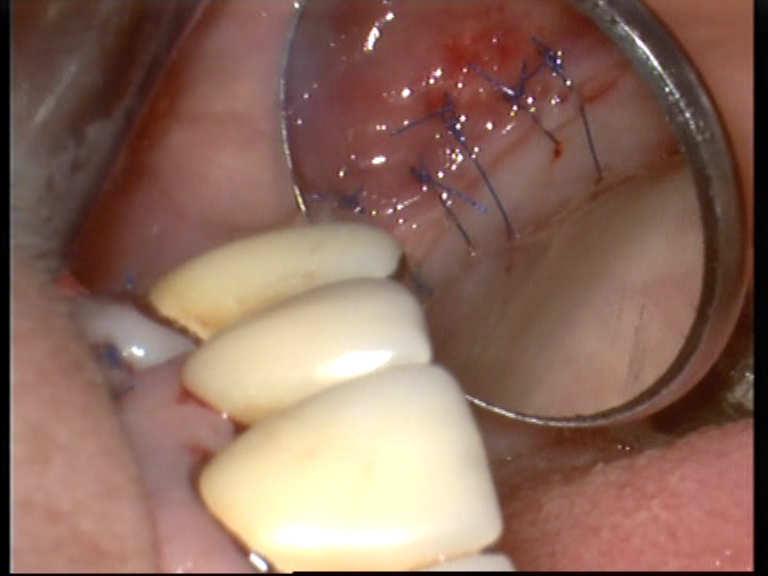

Bone defect filling

While many of the jaw-surgeon-y one(s) heal from alone after surgical interventions and traumatic events, a bone defect filling becomes necessary.

Different procedures are possibly:

The surgical treatment today in most of cases will be done with the Er:YAG laser.